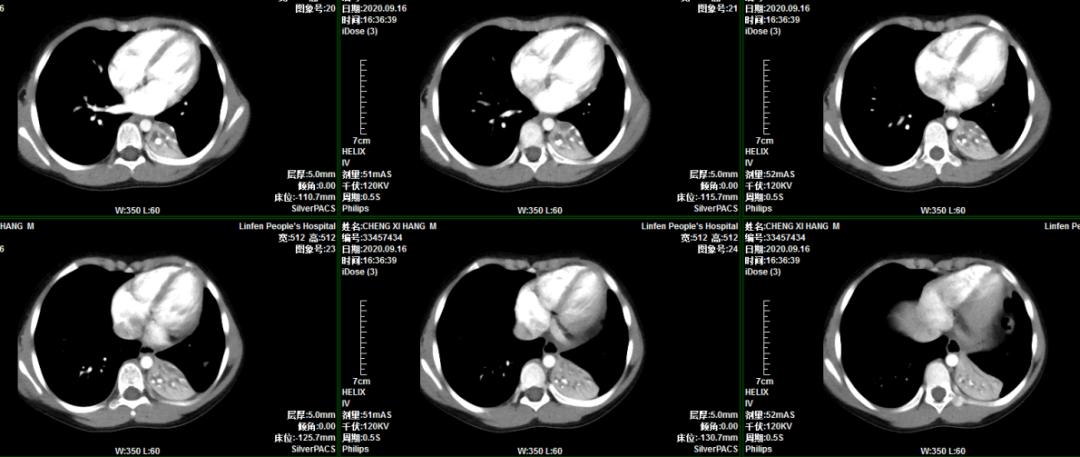

患儿程某,男,6岁3月,主因“间断咳嗽、喘息20天”入住我院普通儿科。入院后行胸部CT示左肺下叶不张,进一步增强扫描考虑左肺下叶支气管存在异物堵塞。考虑病程长,异物位于左肺下叶亚支,难度大。小儿呼吸科李荟主任积极邀请首都医科大学附属北京儿童医院呼吸儿科室杨海明主任、气管镜室李干主任亲临我院会诊指导,顺利进行了支气管镜检查及异物取出术,术后5天复查胸部CT肺不张完全恢复。

术前胸部CT